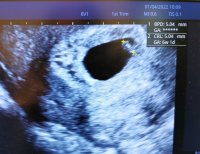

Jeg var ca 5+6 første gangen når hun så bare plommesekken. I dag skal jeg være ca 6+6, hun målte ca 6+4 som hun sa var bra. Og at jeg muligens er ca 6+4/6+5, men kan også være 6+6. Utstyrer er ikke tipp topp, men helt greit.Så deilig utfall

Så ett lite hjerte banke og er så glad for det

. Viste seg å være noen dager bak forventet dato. Så vi bestemte oss for å ikke ta mer blodprøver, heller ny ul neste uke. Og være positive og glede seg over et lite hjerte som banker i magen min